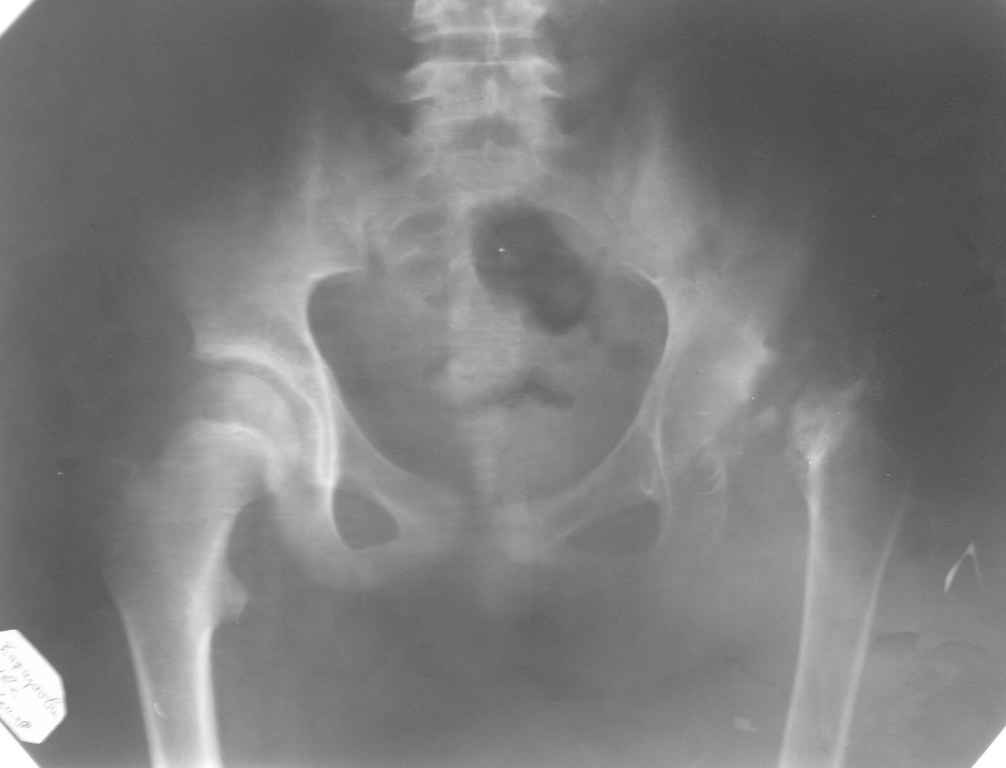

Снимок во вложении по поводу АНГБ

Согласен с Вами что протезирование в детском возрасте крайне не желательно.Необходимо как можно дольше отодвинуть по времени операцию по пересадке сустава (к 25-30 годам)но важно постоянно наступать на ногу что бы избежать атрофии мышц остеопороза кости и анкилоза.

Возможный вариант решения проблемы-

Pelvic support proximal femur osteotomy with maximal adduction of proximal fragment and

Distal femur osteotomy for lengthening and normalization of limb mechanical axis.

Как альтернативу артродезу/ артропластике в детском возрасте при патологии т.б. много работ по двойной вальгизирующей остеотомии бедра , предложенной Илизаровым или pelvic support osteotomy (много статей на google.com)

остеотомий: восстановление опорности ноги, отсутствие болей, исчезновение Тренделенбурга

Уважаемый Гуфрон! В этом возрасте и при подобной деформации не следует опасаться реконструктивных вмешательств на суставе. Один из вариантов: низведение большого вертела и коррекция свода вертлужной впадины, возможно потребуется и артротомия для лучшей центрации головки бедра. АИФ